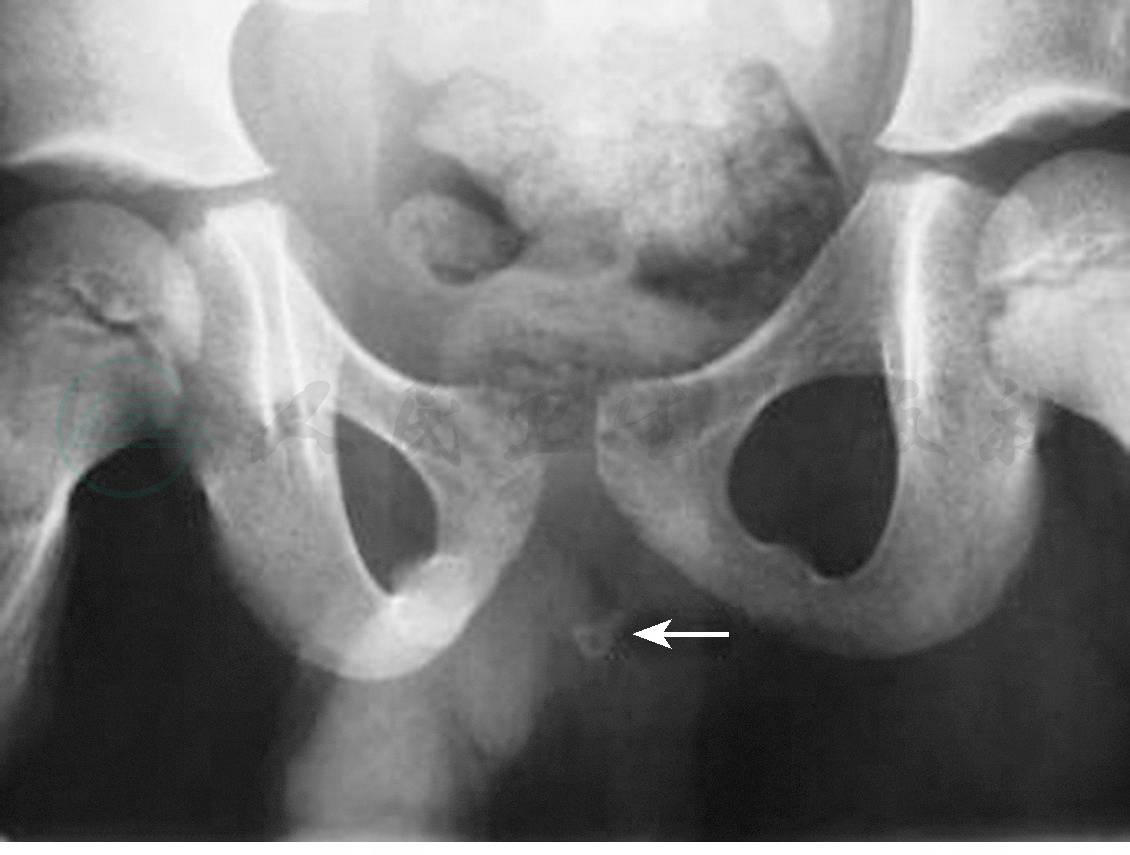

鉴于尿道结石大部分为草酸钙结石,因而传统X线检查可发现大部分结石。由于传统KUB平片往往无法观察到前尿道位置,建议对怀疑尿道结石的患者行盆腔正位X线检查(图1)。对于憩室或尿道狭窄合并尿道结石患者,逆行尿道造影不仅可以发现结石,更可提示尿道腔内及尿道周围组织的病变情况。超声可以明显发现前尿道结石,其声像图表现为尿道腔内强回声团块伴声影,当结石较小时可见结石随液体流动而滚动(图2)。后尿道结石,尤其是前列腺部结石往往在超声影像中误诊为前列腺钙化。这可能与前列腺钙化过于靠近尿道、患者肥胖、超声仪器分辨率低、检查者经验不足等因素有关。如条件许可,建议对怀疑后尿道结石患者行盆腔CT检查,在CT影像学多表现为尿道内高密度影(图3)。但仍注意需与前列腺钙化进行鉴别。盆腔MRI检查同样可发现结石,但MRI检查更大程度上有助于显示结石周围尿道管腔及尿道周围组织的病变情况。因其费用较高,操作时间较长,故而不作为尿道结石诊断的首选方法。

图1尿道结石盆腔正位X线像